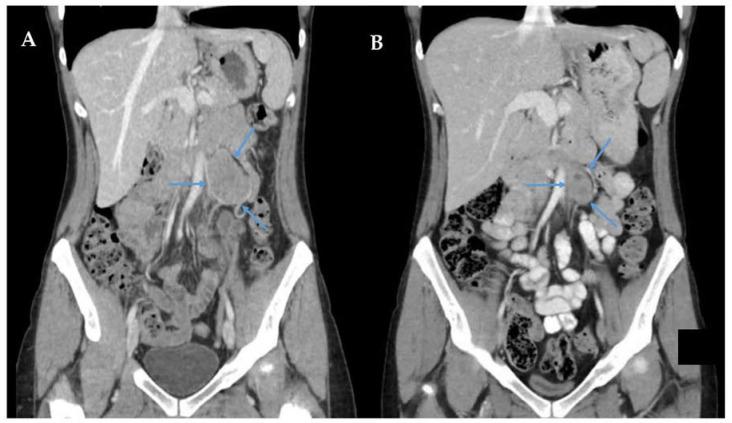

成人超罕见原发性腹膜后软组织肉瘤的实用管理:以血管周上皮样肿瘤和骨外尤文肉瘤为重点。

Practical Management of Adult Ultra-Rare Primary Retroperitoneal Soft Tissue Sarcoma: A Focus on Perivascular Epithelioid Tumours and Extraosseous Ewing Sarcoma.

With the exception of well-differentiated liposarcoma, dedifferentiated liposarcoma, leiomyosarcoma, solitary fibrous tumour, malignant peripheral nerve sheath tumour, and undifferentiated pleomorphic sarcoma, the majority of the ≈70 histologic subtypes of retroperitoneal sarcoma are defined as 'ultra-rare' sarcomas, with an incidence of ≤1-5/1,000,000 persons/year. For most of these ultra-rare RPS subtypes, diagnosis and treatment follows international guidelines for the management of more common RPS histologies, with en bloc surgical resection as the mainstay of curative treatment, and enrolment in clinical trials where possible. Because the treatment of RPS is heavily driven by histology, the surgeon must be familiar with specific issues related to the diagnosis and management of ultra-rare sarcoma subtypes. Expert radiological and surgeon reviews are required to differentiate similarly presenting tumours where surgery can be avoided (e.g., angiomyolipoma), or where upfront systemic therapy is indicated (e.g., extraosseous Ewing's sarcoma). Thus, the management of all retroperitoneal sarcomas should occur at a sarcoma referral centre, with a multidisciplinary team of experts dedicated to the surgical and medical management of these rare tumours. In this focused review, we highlight how diagnosis and management of the ultra-rare primary RPS histologies of malignant perivascular epithelioid cell tumour (PEComa), extraosseous Ewing sarcoma (EES), extraosseous osteosarcoma (EOS), and rhabdomyosarcoma (RMS) critically diverge from the management of more common RPS subtypes.

摘要